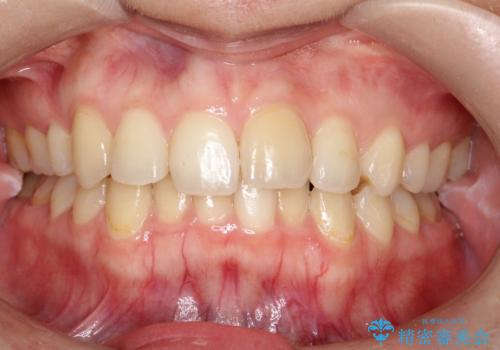

矯正後の後戻り インビザラインで改善

- 前歯のガタツキが気になると来院されました。

マウスピース矯正治療を選択しました。

前歯のガタツキを改善する治療法として、マウスピース矯正が適していることが多いです。

マウスピース矯正は、金属製のブラケットやワイヤーを使用せずに、透明なマウスピースを装着して歯を移動させる方法です。そのため、目立たず、痛みも少ないです。